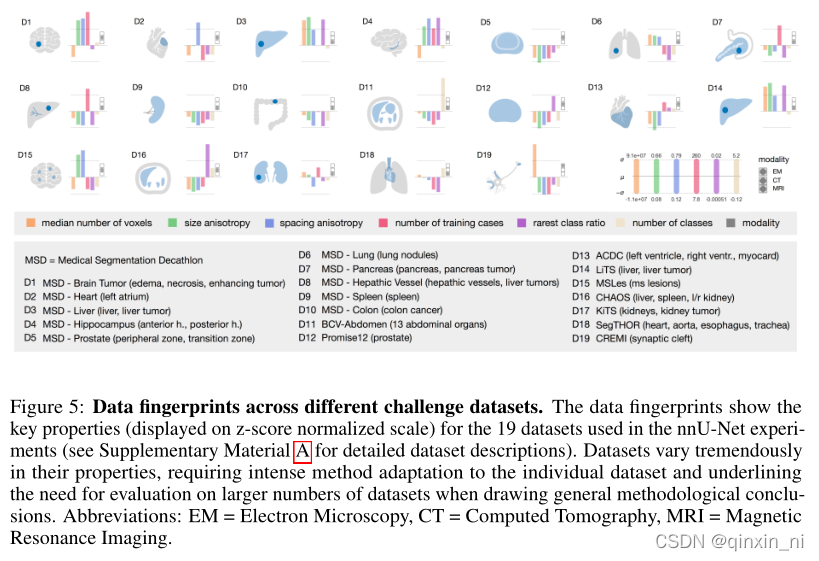

以下是nnUNet在19个数据集上的“管道指纹”(附录A),可见“管道指纹”体现了数据集的关键性质(displayed on z-score normalized scale)。数据集在他们的属性上体现出了巨大的差异,所以一方面需要很努力的适应不同的数据集,另一方面需要很大量的数据的支撑来得到其方法结论。右下角时三个模态。

我们抽取了19个实验数据集和相对应的“管道指纹”,并展示在图五中。这记录了在医学图像领域,数据集具有超乎寻常的复杂性。同时也暴露了为什么其他算法不如nnUNet的原因:

我们进行一次“管道指纹”的设计,要么就是人为的设置,要么就是利用各个“数据指纹”之间的隐藏关系进行设置。结果可能就是,对于一个数据集来说优化的效果很好,而对于其他数据集可能没有什么作用,对于一个新的数据集,就需要人为的不断的进行再建计划和再次优化。比如图片的尺寸会影响patch_size,patch_size会反过来影像网络的拓扑结构(下采样的次数和卷积核的尺寸等),而网络的拓扑结构将再次影响其他的超参数。